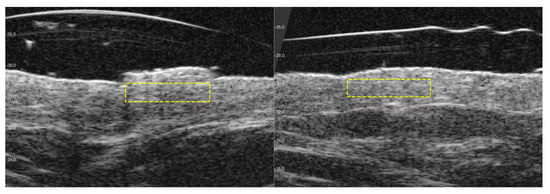

3.3. Visible and Ultrasound Changes in Scar Area